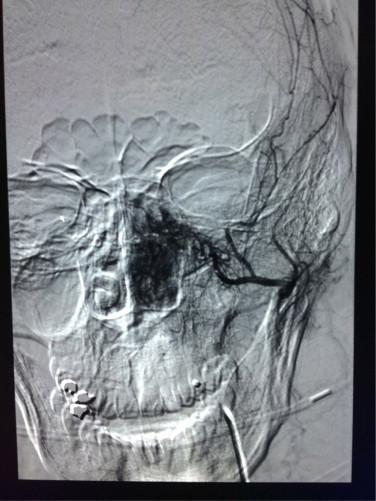

Our patient was a 32-year-old man with a chief complaint of recurrent left-sided epistaxis for one year, brisk and continuous for ten days prior to presentation, subsequently found to have a 4cm vascular skull base tumor causing mild expansion of the pterygopalatine fossa. The patient underwent pre-operative embolization utilizing 300-500micrometer microspheres injected into the ipsilateral maxillary artery. The following day, the patient underwent definite Stereotactical surgical resection of his JNA tumor. Estimated blood loss during the operation was 50mL, and the patient was discharged the same day.

我们的患者是一名32岁男性,主要症状为反复左侧鼻出血1年,就诊前10天出血活跃且持续,随后发现有一个4厘米的血管性颅底肿瘤,导致翼腭窝轻度扩张。患者接受了术前栓塞,将300 - 500微米的微球注入同侧上颌动脉。第二天,患者接受了JNA肿瘤的确定性立体定向手术切除。术中估计失血量为50毫升,患者当天出院。